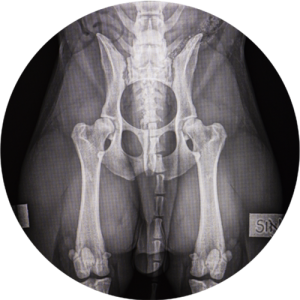

Kennelliiton viralliset tutkimukset

Ennen Kennelliiton virallisia tutkimuksia (viralliset lonkka- , kyynär- ja selkäkuvat) on omistajan tehtävä sähköinen ennakkolähete Kennelliiton Omakoira-palvelussa tai Omakoira-mobiilisovelluksessa. Vuoden 2022 alusta klinikka ei enää tee lähetteitä, vaan omistajan on tehtävä ne ennen tutkimuksiin tuloa. Ohjeet lähetteen tekemiseen löydät Kennelliiton sivuilta.